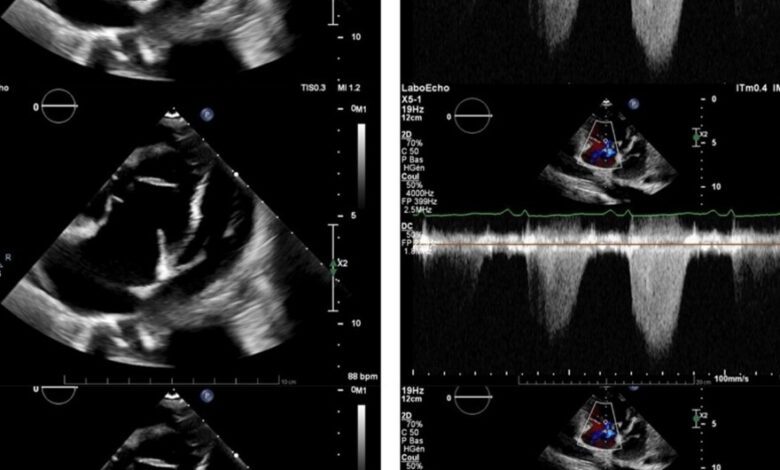

Анализы крови выявили анемию и биохимические признаки сердечной недостаточности. Дополнительные исследования позволили исключить тромбоэмболию легочной артерии, а эхокардиография показала, что левый желудочек сдавлен расширенным правым. Давление в легочной артерии оказалось значительно выше нормы, что подтвердило диагноз легочной гипертензии.